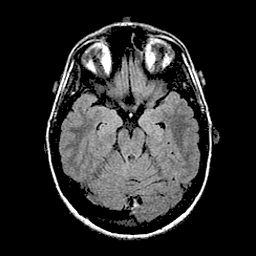

基于深度学习分割算法的 PyTorch 实现的 U-Net,用于脑部 MRI 中 FLAIR 异常区域的分割。该算法曾应用于论文《低级别胶质瘤基因组亚型与深度学习算法自动提取的形状特征之间的关联》(https://doi.org/10.1016/j.compbiomed.2019.05.002)。

用于开发和评估的数据集已在 Kaggle 上公开:kaggle.com/mateuszbuda/lgg-mri-segmentation。该数据集包含来自 TCIA LGG 收藏 的 MR 图像,并附有杜克大学认证放射科医师标注的分割掩码。